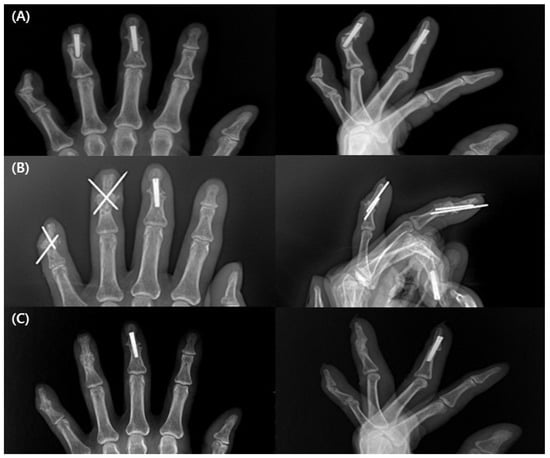

All patients had complete bone union at the final follow-up (Figure 3). The mean duration of bone union was 9.2 (±2.5) weeks (range, 7–16 weeks). One patient had delayed union, with 16 weeks of bone union.

Figure 3. A 62-year-old woman underwent 3rd, 4th, and 5th distal interphalangeal joint (DIP) arthrodesis. (A) At 16 weeks after the initial surgery, pain and tenderness were sustained and radiograph shows no evidence of union with 4th and 5th DIP joint. The 5th finger was secured with K-wires, and the 3rd and 4th fingers were secured with Acutrak screws at initial surgery. (B) Post revision surgery with K-wires and inlay technique with cortico-cancellous olecranon bone graft. (C) The bony union achieved radiographically at 6 weeks after the revision surgery.